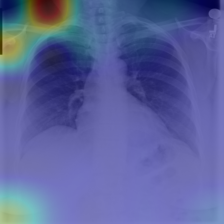

COVID data set. The potential of artificial intelligence and especially deep learning in medicine is huge (EJ., 2019). On the other hand, the medical domain is known to be badly affected by the presence of confounders (Jager et al., 2008; Smith & Nichols, 2018). In order to evaluate the potential of ProtoPDebug to help addressing this issue, we tested it on a challenging real-world problem from the medical imaging domain. The task is to recognize COVID-19 from chest radiographies. As shown in DeGrave et al. (2021), a classifier trained on this dataset heavily relies on confounders that correlate with the presence or absence of COVID. These confounders come from the image acquisition procedure or annotations on the image. We trained and tested ProtoPDebug on the same datasets used in DeGrave et al. (2021) using the data pipeline source code (cod, 2021a). To simplify the identification of confounders, we focused on a binary classification task, discriminating COVID-positive images from images without any pathology. Given the extremely high inter-annotator agreement of the CUB5nat experiment, this experiment was conducted internally in our lab. We leave a crowdsourced evaluation to an extended version of this work.

Results. Fig. 5 reports the (non-zero activation) prototypes of ProtoPDebug at different correction rounds. As for Fig. 4 (left), the left-most column corresponds to the prototypes learned by ProtoPNets. Note that for each prototype, the supervision is given to the 10 most-activated images (). Penalized confounders have been extracted from images on which the prototype has non-zero activation, because they influence the classification. However, the patches of the images to remember are extracted even if the activation is zero, in order to force the prototype to increase the activation on them thanks to the remembering loss. Eventually, ProtoPDebug manages to learn non-confounded prototypes, resulting in substantially improved test classification performance. The test goes from 0.26 of ProtoPNets (first column) to 0.54 at the end of the debugging process.